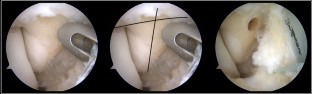

During diagnostic arthroscopy, 12 patients showed an isolated anterior talofibular ligament (ATFL) injury, and in one patient, both the ATFL and calcaneofibular ligament were affected. Arthroscopic examination of the deltoid ligament demonstrated a tear affecting the anterior area of the ligament in all cases. The tear was described as an "open book" tear, because the ligament was separated from the medial malleolus when applying passive internal rotation of the tibio-talar joint. This gap was closed when the tibio-talar joint was in neutral rotation or externally rotated. All patients reported subjective improvement in their ankle instability after the arthroscopic all-inside ligaments repair. The median AOFAS score increased from 70 (44–77) preoperatively to 100 (77–100) at final follow-up.

Fig. 2